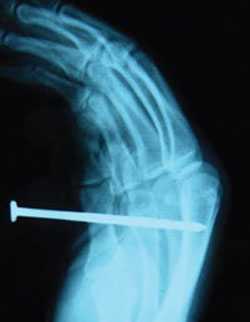

Radiografía de una lesión causada por pistola de clavos